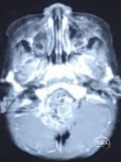

术后6月MRI

术后3月及6月复查未见肿瘤复发。但术后6月复诊时家属诉患儿近日不愿独自站立,行走时常需家人牵手。进一步复查CT显示脑室有扩大趋势。遂决定实施脑室腹腔分流手术,术后站立行走有改善。